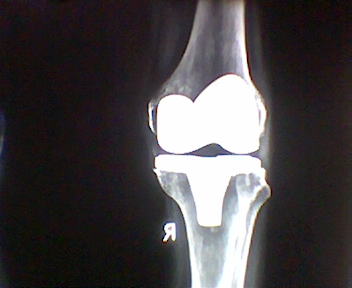

Knee Replacement Suregery

- Fixed Bearing, Rotating Platform, All –Poly Posterior Stabilised, Hinged Knee Replacement

- Revision Joint Surgery

- Correction Of Very Severe Deformities